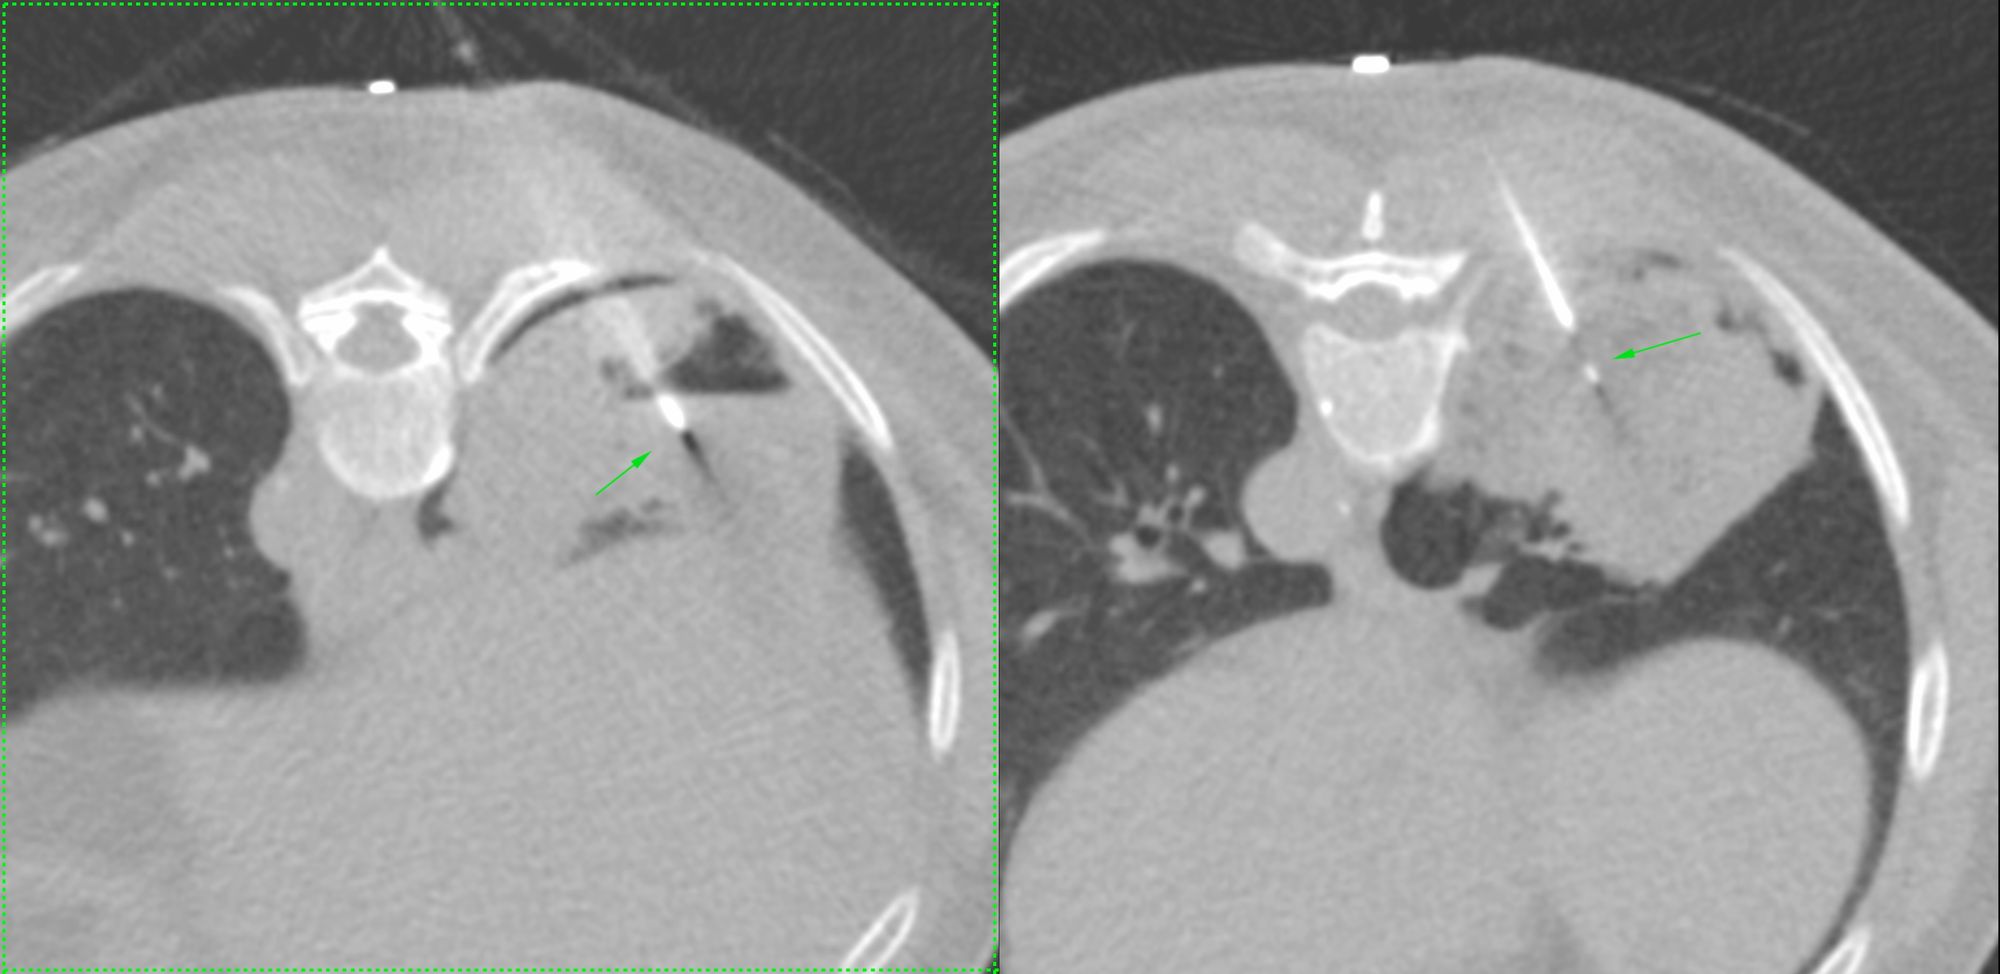

Case 12: Right Iliac Bone Biopsy - Multifocal Bone Lesions

Bhavin Jankharia - 13 March 2021

Case 10: Right Ischial Tuberosity Lesion Biopsy

Bhavin Jankharia - 07 March 2021